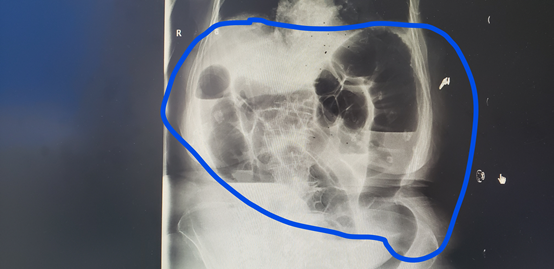

▲入院时候的腹部平片

(蓝圈圈里面都是气体和粑粑)

▲蓝圈圈内可见肠梗阻基本完全解除

红圈内支架也已经完成撑开